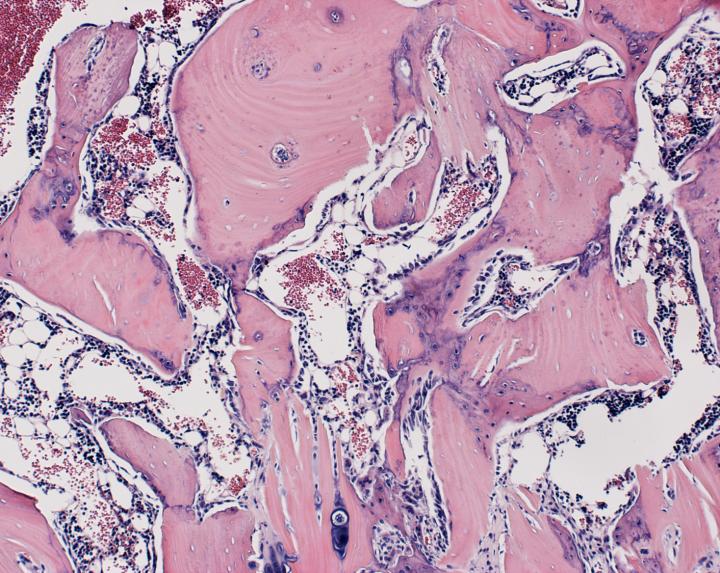

image: Bone formation in the rat spine.

After four weeks, the researchers studied the rats' spinal tissue and observed continued high levels of the WISP-1 protein. They also observed new bone forming, successfully fusing the vertebrae together, whereas the rats not treated with stem cells making WISP-1 did not show any successful bone fusion during the time the researchers were observing.